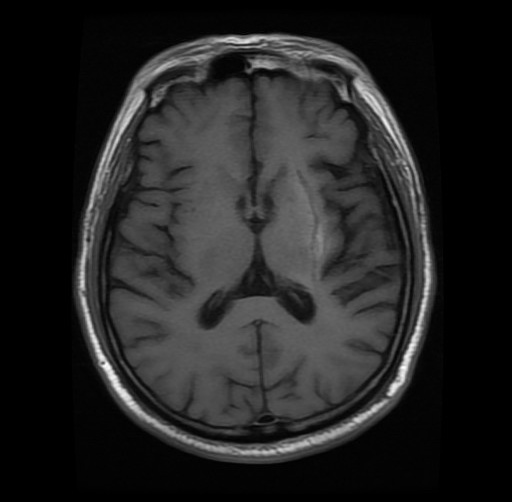

右:术后可见血肿完全清除

术后第1天,老杨右侧肢体肌力即明显改善,术后第8天在他人搀扶下可以正常行走,并恢复了正常言语功能,第40天老杨已经可以独自在小区闲逛。